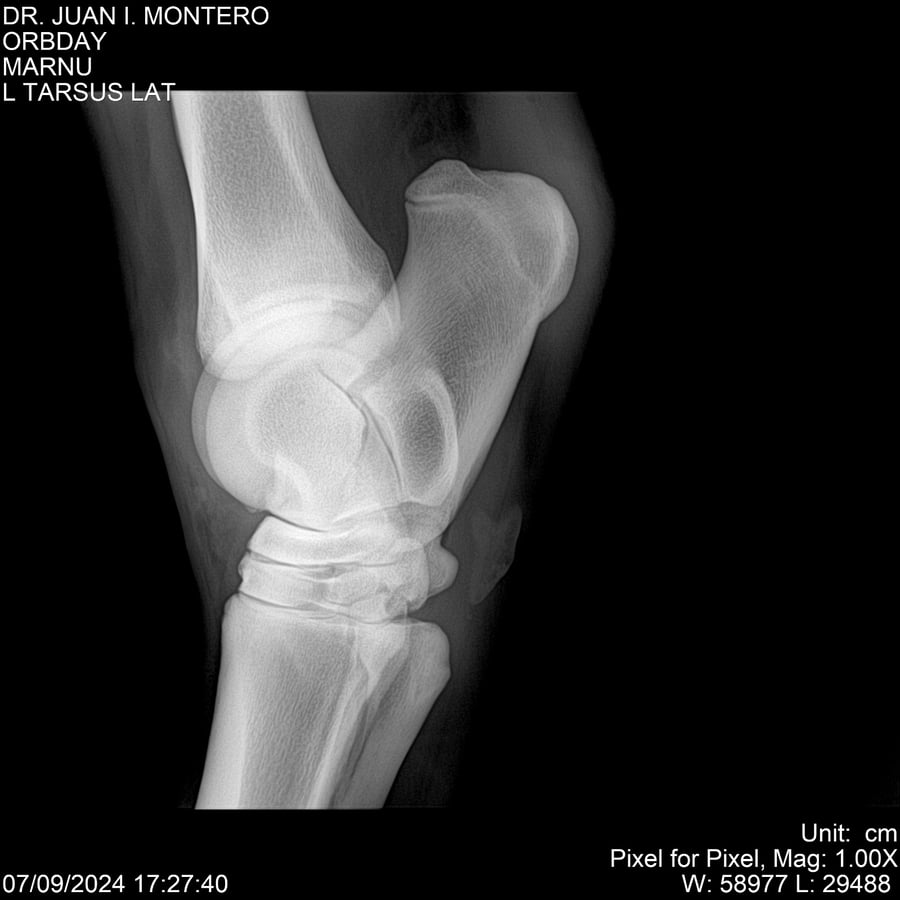

• Empresa: Abelenda N. R., Walter Hugo